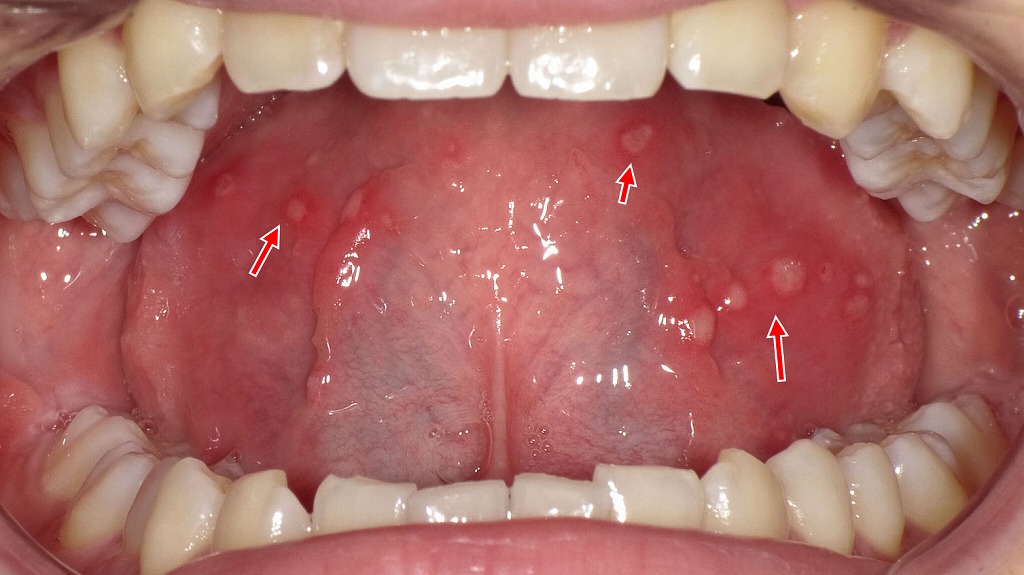

舌にできた痛みの強いアフタ性口内炎

画像には、舌の表面に白っぽく抜けたような円形の病変が2か所見られます。周囲はやや赤みを帯び、典型的な**アフタ性口内炎(アフタ性潰瘍)**の所見とよく一致します。

🔍 詳細な観察ポイント

- 部位:舌の側方~中央寄り

- 大きさ:およそ 5mm 前後

- 形状:境界明瞭な円形

- 色調:中心が白~黄白色、その周囲が赤く縁取られている

- 表面:浅いびらん(粘膜が剥がれている)

- 数:2つ(多発性アフタの可能性)

🦷 考えられる疾患(最も典型的なのは…)

アフタ性口内炎(アフタ性潰瘍)

- 食事・歯ブラシ接触で痛みやすい

- ストレス・ビタミン不足・免疫低下時に起こりやすい

- 数日~2週間で自然治癒することが多い

- 舌にできやすいタイプ

⚠️ 注意すべき点

次のような場合は別疾患の可能性もあるため、歯科受診が望ましいです:

- 2週間以上治らない

- 痛みが非常に強い

- 病変が増える・広がる

- 周囲に硬さを伴う

- 再発を繰り返す

💡 一般的な対処

- 刺激物(辛い物・熱い物・酸味)は避ける

- ビタミンB群補給

- 市販の口内炎パッチ・軟膏

- 痛みが強い場合はレーザー治療も有効(歯科で対応可)